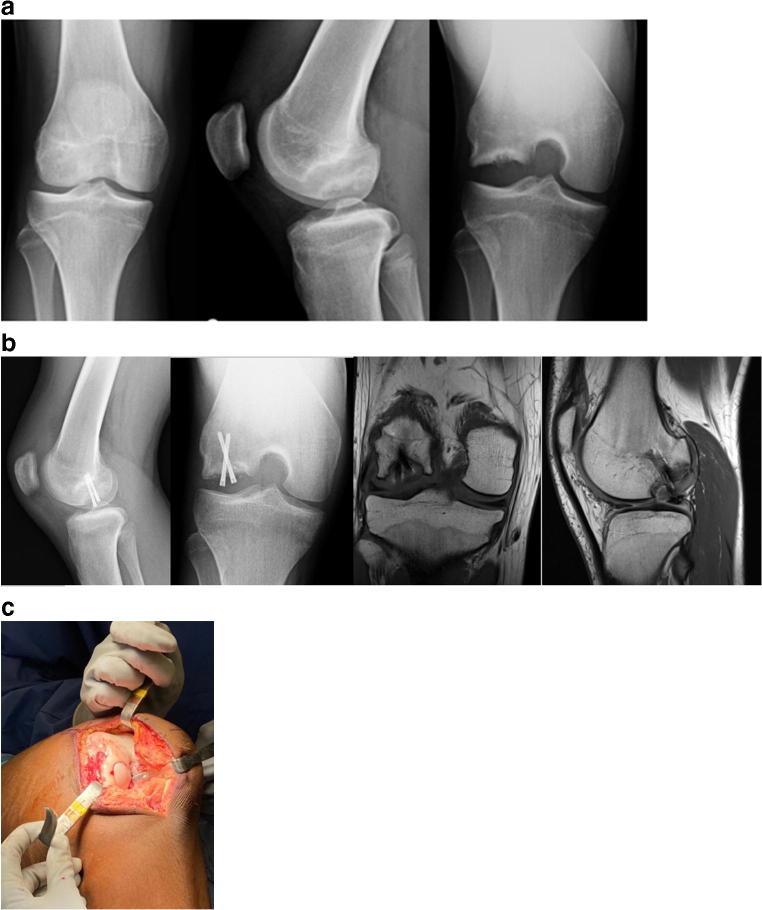

Salvage techniques are necessary when an OCD lesion fails to heal with appropriate treatment (Fig. 1) or that presents in an unsalvageable state with fragmentation of the progeny fragment, a loose body, or with extensive cartilage deterioration. Salvage techniques include debridement, microfracture, osteochondral grafting, or autologous chondrocyte implantation.

Fig. 1.

15-year-old male with OCD of the lateral femoral condyle (a) initially treated with curretage, grafting, and fixation. He had incomplete healing on MRI, radiographs (b) and arthroscopy at 5 months post-op. He later underwent osteochondral allograft transplantation as a salvage surgery 6 months after his initial surgery (c)